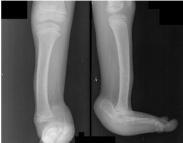

先天性肌缺如(congenital absence of muscles)臨床上比較少見,是由于胎兒本身發育異常,或因在宮內受到機械阻礙所致。常表現為單塊肌肉部分或全部缺如,也可表現為某一組肌肉的缺如。如果缺如的肌肉不能被其他正常肌肉所代償,則可能出現畸形。